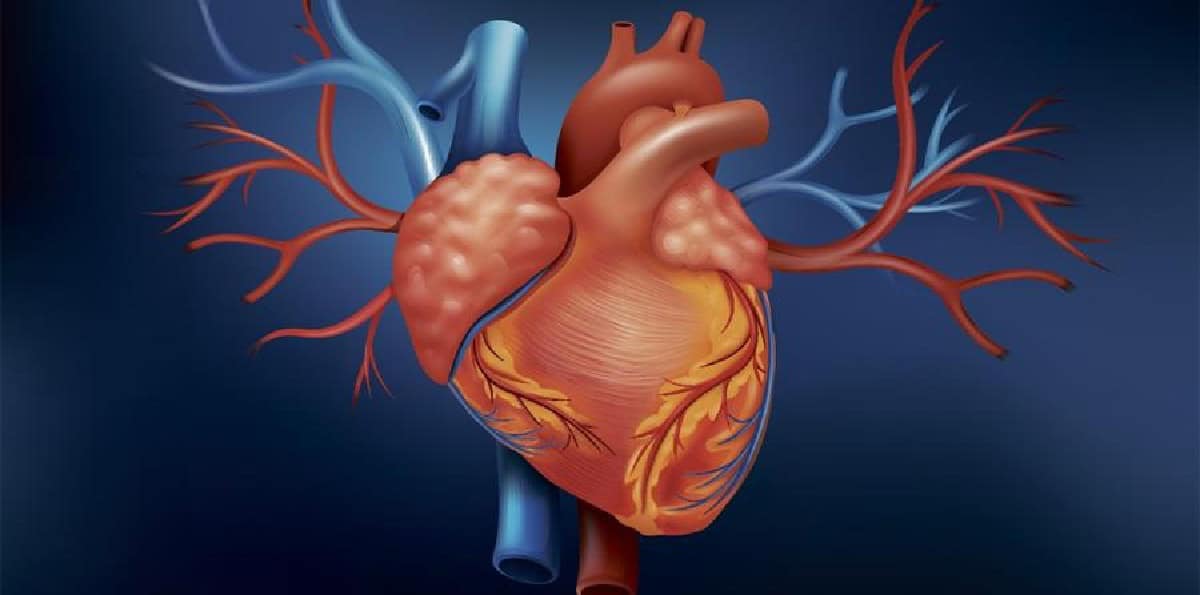

وطن– صمامات القلب هي هياكل تنظم تدفق الدم بين حجرات القلب والشرايين، وعندما يتلف أو يضعف واحد أو أكثر من هذه الصمامات، فإنها يمكن أن تؤدي إلى مرض صمام القلب، ما يؤثر على الوظيفة الطبيعية للقلب ويمكن أن يسبب مضاعفات خطيرة.

وبحسب مجلّة “لا فيدا لوثيدا” الإسبانية، فإن مرض صمام القلب يمكن أن يكون خلقيًا (موجودًا منذ الولادة) أو مكتسبًا (بسبب العدوى أو الشيخوخة أو عوامل الخطر مثل ارتفاع ضغط الدم أو ارتفاع الكوليسترول). ناهيك بأن بعض الحالات قليلة الحدّة ولا تتطلب علاجًا، بينما قد تتطلب حالات أخرى علاجًا أو تدخلاً جراحيًا.